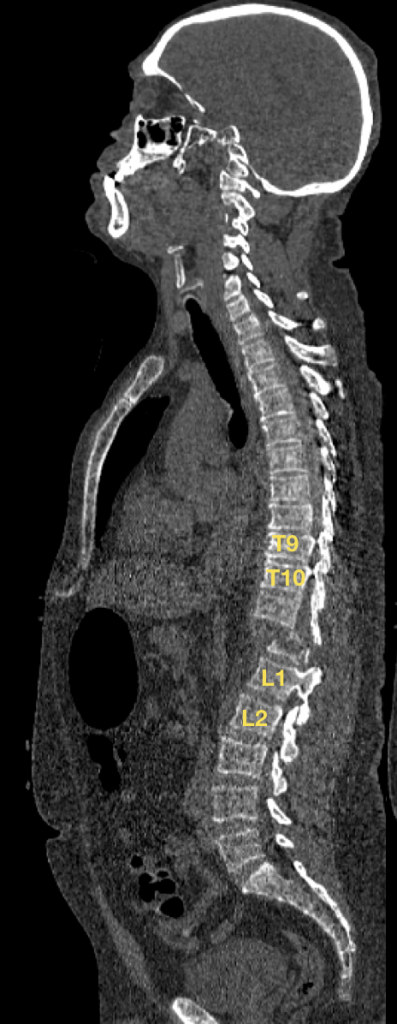

Paciente: FBM

Edad: 50 años

Diagnóstico: Fractura Traumática de Vertebras Torácicas T11 y T12. Clasificación AO: C3.N3.M1, TLICS: 9 puntos, ASIA B

Tipo de Cirugía: Reconstrucción Espinal Avanzada, mediante Instrumentación transpedicular T9-T10 a L1-L2, con descompresión medular microquirúrgica T11-T12

Fecha de la cirugía: Diciembre 23 del 2017